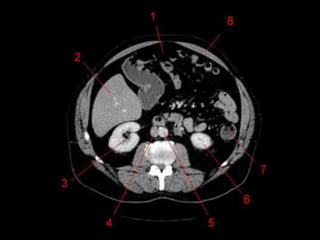

Subdivisão Funcional • Osoito segmentos são divididos: – A primeira divisão é realizada dividindo através da Porta Hepática, em esquerdo (I a IV) e direito (V a VIII) – A divisão é feita baseada em um relógio – Caudado é o segmento I – No ‘lobo’ esquerdo, o IV separa-se do II e do III pela veia hepática esquerda, representado anatomicamente pelo ligamento falciforme. – II e III se dividem através de uma linha imaginária transversal na altura da porta hepática. – No ‘lobo’ direito, se divide os segmentos através de uma linha transversal e pela veia hepática direita.

Subdivisão Funcional • Fundamentalimportância para Ressecção. • Maioria das lesões são do fígado direito.

Vasos Hepáticos • Veiaporta – Formada pela união da Veia Esplênica e Mesentérica Superior • Artéria Hepática – Segmento da Tronco Celíaco – Dividida em Comum e Própria pelo surgimento da artéria gastroduodenal. • Na maioria das pessoas, a artéria é anterior a veia (91%). Na maioria das pessoas, a artéria hepática direita passa atrás do ducto hepático comum. (64%)

Técnicas de Imagem •US: Primeiro exame pedido ao: 1) dor no hipocondrio direito; 2) testes de função hepáticas anormais; 3) suspeita de malignidade. • TC: Tres fases – Arterial (10 a 20 segundos) – Fase venosa portal ( 30 segundos ) – Fase venosa hepática (60 segundos) • TC Portografia: Metastases.